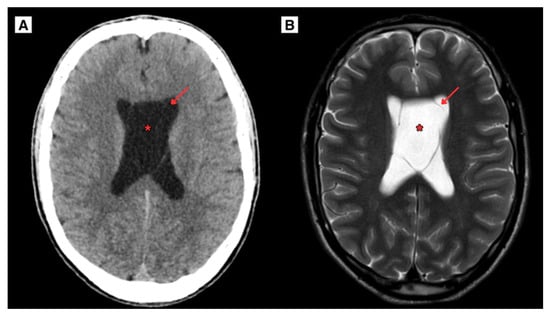

The CT scan of the 20-year-old patient brain demonstrated the presence of both CSP and CV cyst, representing a dilated ventricles, occlusive hydrocephalus without edema (Figure 1). Follow-up MRI scan of the brain revealed obstructive hydrocephalus with progressive ventricular enlargement (Figure 2).

Figure 1.

(A) CT scan of the brain of a 20-year-old Caucasian male in the axial plane (2024). Demonstrated enlargement of the CSP and CV cysts forming with arched membranous leaves, with the maximum diameter measuring approximately 30 mm, indicating an increase of roughly 17.8 mm. (B) MRI scan of the brain revealed CSP and CV cysts and hydrocephalus, presenting with progressively worsening symptoms over several months including increasing headaches and dizziness. The cysts developed from the CSP and CV leaves. Red arrow—septum pellucidum wall, Red asterisk—cavum septum pellucidum.